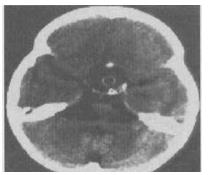

- 单项选择题2、 女性,12岁。视物模糊8个月,伴多饮多尿,月经未来潮。CT检查如图,请根据CT图像给出正确诊断()。

A、动脉瘤

B、颅咽管瘤

C、错构瘤

D、垂体瘤

E、脑膜瘤